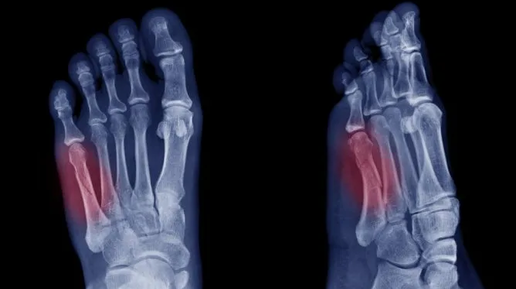

При подобном типе перелома страдает пятая плюсневая кость. Опасность заключается в том, что часто боль и отек принимают за растяжение связок, что усугубляет проблему. Как долго восстанавливаться после перелома Джонса и всегда ли необходима операция? Перелом Джонса случается, когда вы ломаете пятую плюсневую кость, соединяющую мизинец с основанием стопы. Подобный перелом характерен для спортсменов, а также может произойти в результате падения. Лечение включает как консервативные методы, так и хирургическое вмешательство...

Так случилось, что пришлось столкнуться с переломом пятой плюсневой кости левой стопы. Конечно же, хотелось как можно скорее вернуться в строй и обойтись без серьезных последствий - травматологи, с которыми...